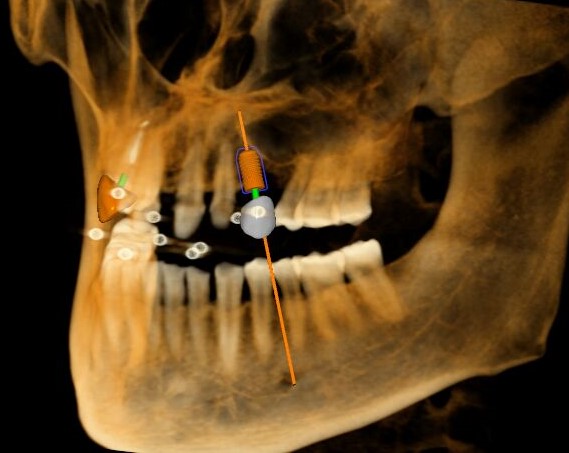

冠狀面視圖

三維視圖

根據(jù)患者CT顯示,使用種植導(dǎo)航軟件設(shè)術(shù)前手術(shù)方案??紤]到患者拒絕手術(shù)摘除上頜竇囊腫等因素,此次手術(shù)選用了Straumann骨水平4.10*8.0mm的植體,植體末端位點(diǎn)設(shè)計(jì)距上頜竇底壁2mm處的同時(shí)兼顧種植方向和修復(fù)間隙,來(lái)達(dá)到理想的效果。